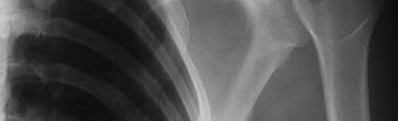

A 70-year-old woman falls down a flight of stairs and sustains the injury shown in Figures A and B to her dominant upper extremity. She lives alone and has no other medical history. Which of the following surgical options is best to minimize complications for this fracture pattern?

This patient has a complex proximal humerus fracture with metaphyseal comminution and poor bone stock. Cemented reverse total shoulder arthroplasty (rTSA) using a long stem prosthesis and tuberosity repair is indicated.

Proximal humerus fragility fractures are hard to treat because of comminution and poor bone stock. AVN is common with glenohumeral fracture-dislocation. Hemiarthroplasty (and standard total shoulder arthroplasty, TSA) is unreliable because of dependence on tuberosity healing. rTSA is recommended for fractures in patients >70 years with severely comminuted fractures, high likelihood of head AVN, and poor tuberosity bone quality (osteoporosis or comminution).

Bufquin et al. retrospectively reviewed the use of rTSA for treatment of 43 patients with 3- and 4-part proximal humerus fractures. They found satisfactory elevation (97°), ER in abduction (30°), constant scores (44) and modified Constant scores (66%). Complications included calcification (90%), tuberosity displacement (53%) and scapular notching (25%). They concluded that rTSA was a good procedure because it provides pain relief and easier functional recovery in spite of failed tuberosity healing.

Anakwenze et al. systematically reviewed acute proximal humerus fractures. Frequency weighted range of motion was flexion 122°, abduction 97°, ER at neutral 18°. Tuberosity repair yielded higher ER compared to no repair.

Scapular notching was the most common complication (32%). They concluded that rTSA patients tended to be elderly women with 4-part fractures, had good pain control but residual dysfunction.

Jobin et al. reviewed rTSA for management of proximal humerus 3- and 4-part fractures. They note >50% of cases have tuberosity resorption. They recommend repairing the greater tuberosity to restore infraspinatus/teres minor function which improves external rotation strength. Greater tuberosity malunion is not a result of secondary displacement, but rather, from intraoperative malreduction. Lesser tuberosity repair should be performed if there is significant bone loss or intraoperative anterior instability.

Figures A and B are AP radiograph and 3D reformatted CT scan showing comminuted proximal humerus fracture dislocation. Illustration A shows rTSA performed with distal cementation of a long stem prosthesis and cerclage fixation of the proximal shaft and the tuberosity fragments.

Incorrect Answers:

Answer 1: ORIF has potential complications of screw cut out, AVN, fracture collapse, tuberosity resorption and loss of fixation. The risk of AVN (and resultant screw cut out) is high because of comminuted fracture-dislocation. Answer 2: Cementing is indicated because metaphyseal fracture bone loss compromises stem fixation.

Answer 3: Greater tuberosity repair improves external rotation strength. Lesser tuberosity repair adds to anterior stability.

Answer 5: Proximal humeral replacement is only necessary for tumor or unreconstructable fractures. They have poorer outcomes because of loss of rotator cuff function.